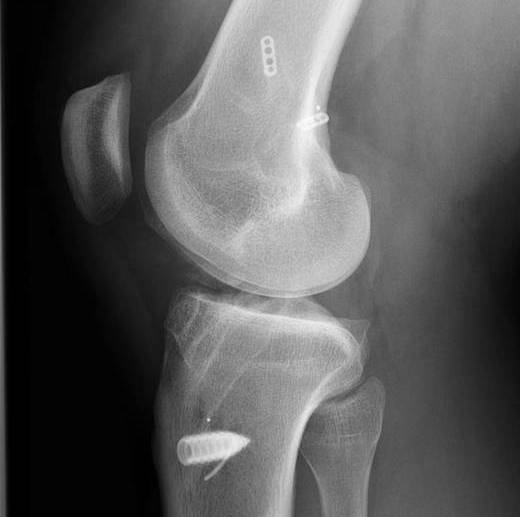

Patient with traumatic failure ACL, previous hamstring with endobutton and bioabsorbable screw

Graft likely too vertical, evidence of tibial tunnel lysis